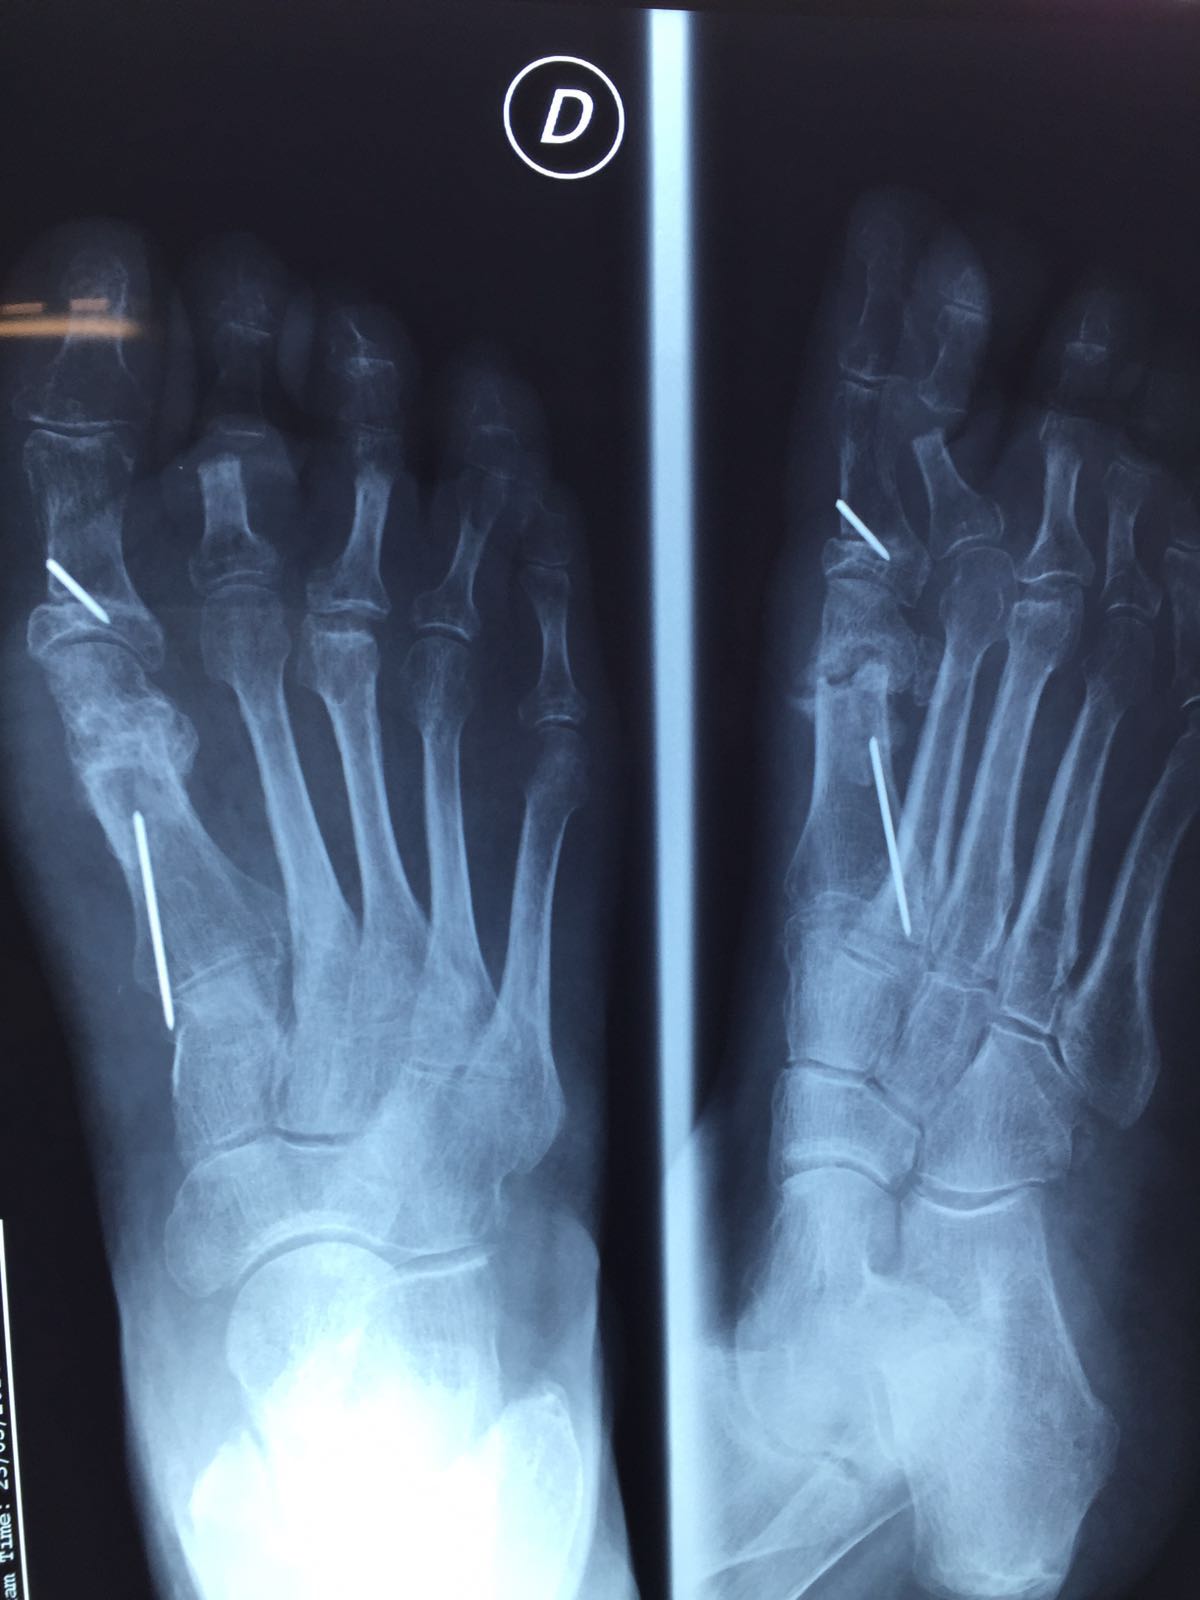

Si os fijáis de la primera a la última foto, podéis ver el proceso de migración. La aguja debería estar fijando la osteotomía, no estaba fijando nada, se escurrió por la diáfisis del metatarsiano y salió por la planta del pie a nivel del arco longitudinal interno en su parte mas proximal, todo un problema para sacarla y localizarla pues no se palpaba bien.

Fijaros en la Rx como va migrando la aguja.

En esta foto se ve claramente como ha migrado, la osteotomía Akin está sin fijar y comienza a salir plantarmente por la diáfisis.